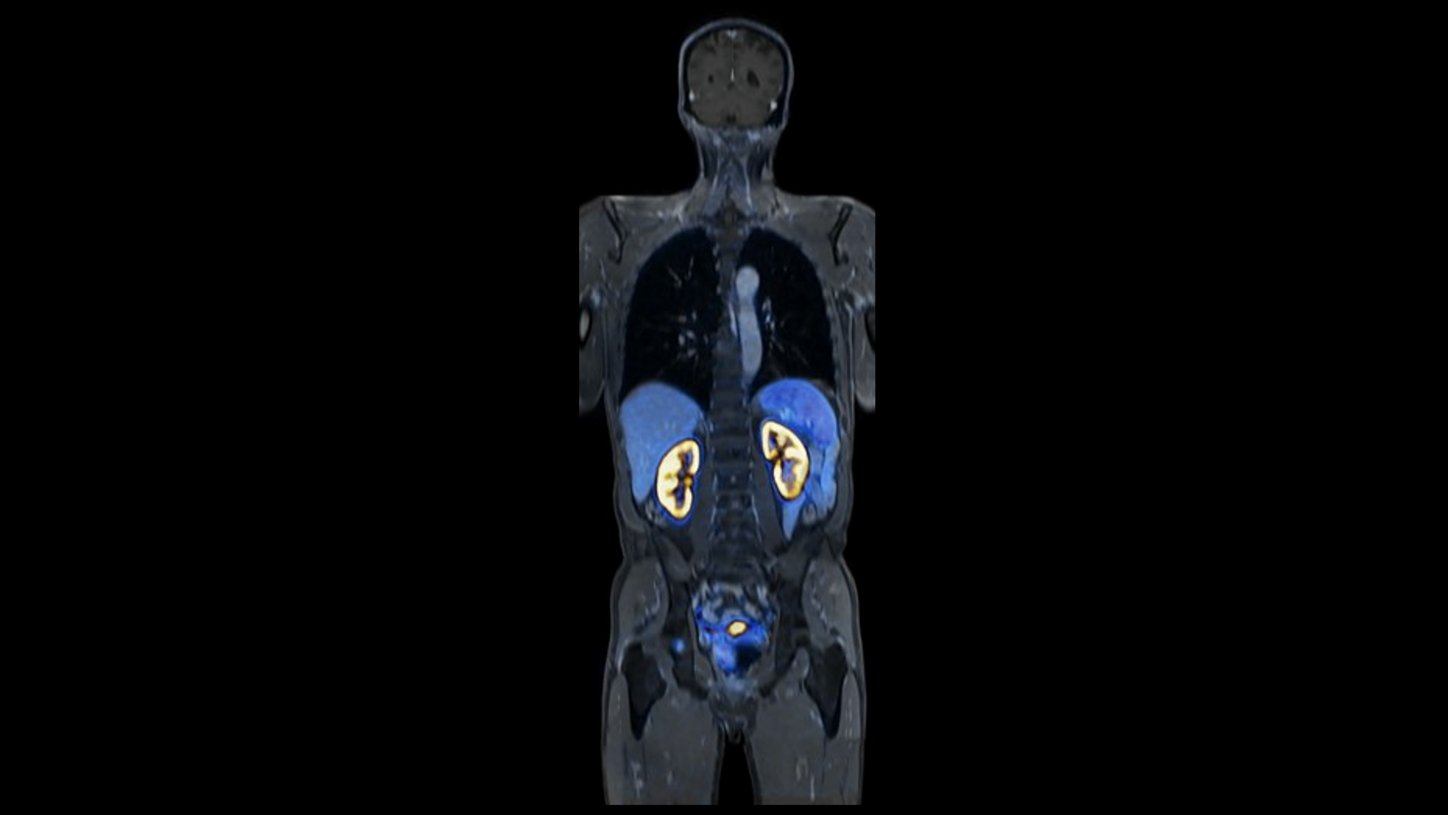

BIOGRAPH One is designed to support one patient-centric pathway to personalized care. By seamlessly integrating PET and MR into one comprehensive exam, it will support clinicians from diagnosis and staging, through a personalized therapy decision to regular therapy assessments to excel precision and support one streamlined approach.

BIOGRAPH One is designed to excel in PET/MR precision to support confident diagnostic decisions. Featuring the Optiso UDR Pro detector with the largest 35 cm axial FOV2 in PET/MR, it is designed to enable comprehensive capture with excellent sensitivity and ultra-fast TOF3 in real time – delivering clear, detailed images.